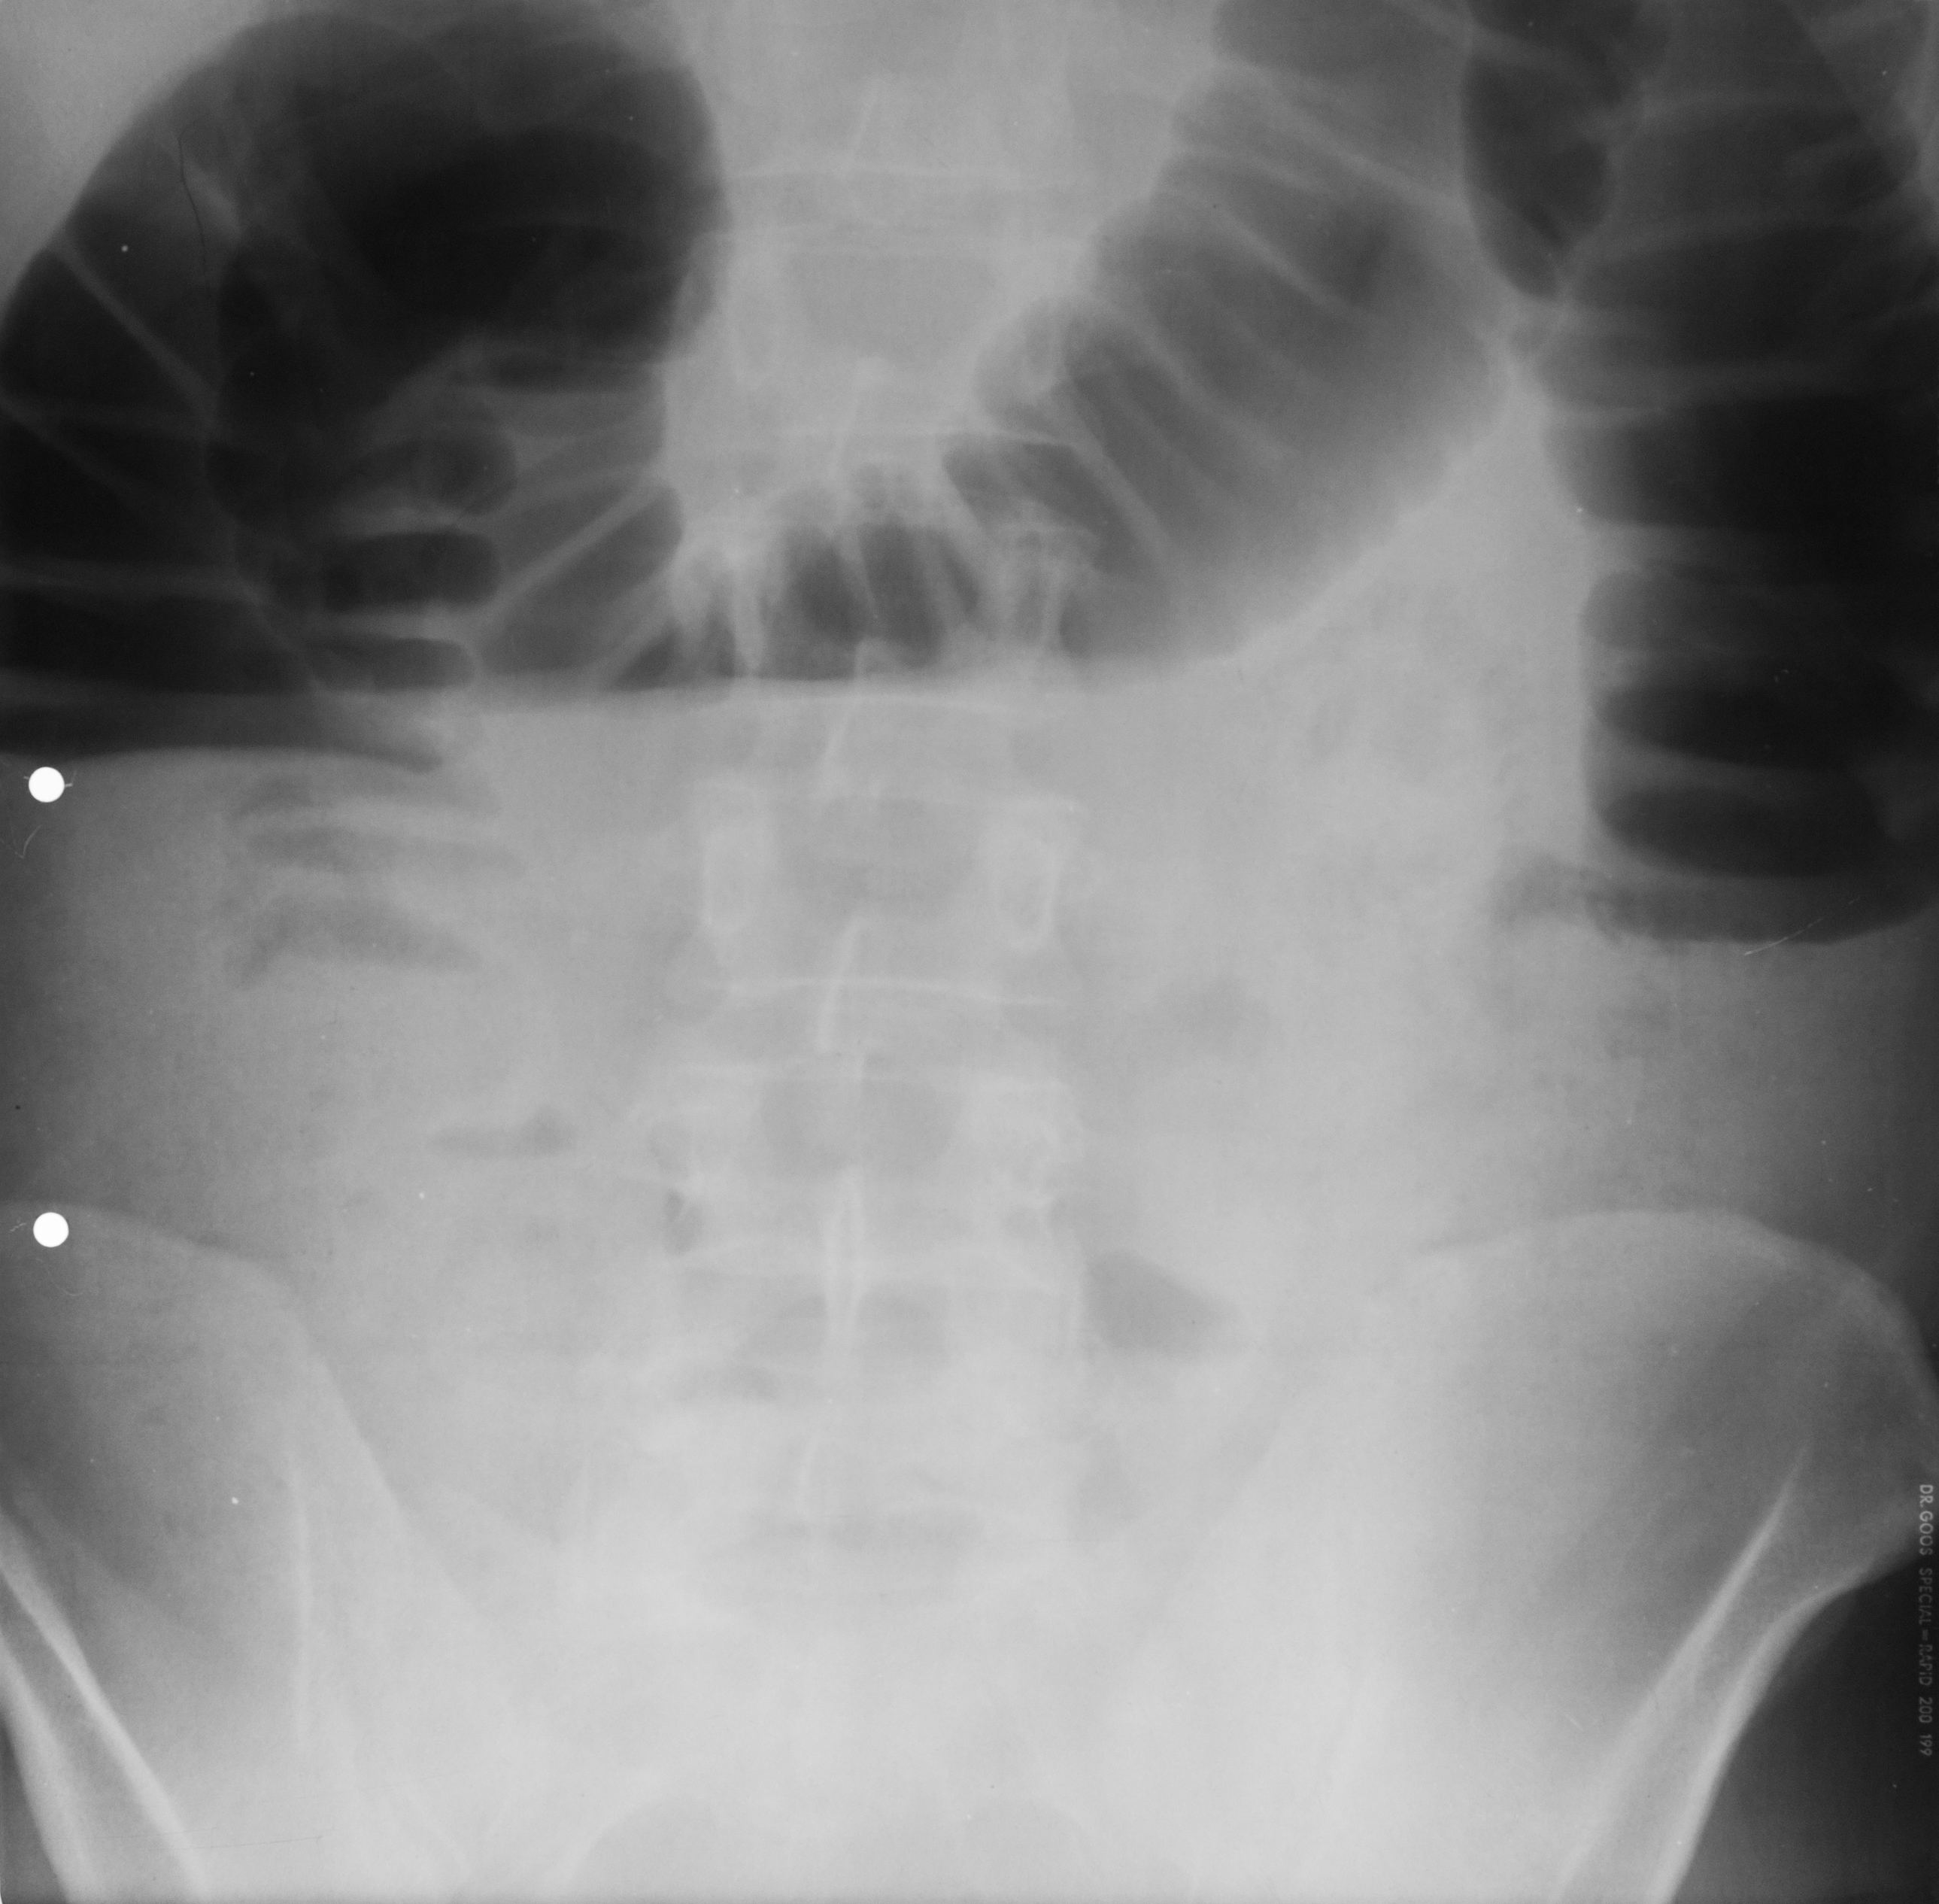

OCLUZIE LA NIVELUL INTESTINULUI SUBȚIRE

Radiografie abdominala pe gol, in etajul mijlociu, multiple imagini hidroaerice, cu ax transversal hidroaeric, cu ax transversal mai mare decat axul craniocaudal. Nivele hidroaerice de tip intestin subtire

OCLUZIE(situată mai jos) SAU ILEUS DINAMIC

Nivele hidroaerice de tip intestine gros, cu ax mare vertical si nivele hidroaerice de tip intestin subtire, posibil ocluzia este undeva mai jos sau sa fie Ileos dinamic

Imagine hidroaerica tipica de intestine gros, ax mare vertical, ax mare vertical mai mare decat ax orizontal, se vad haustrele deci clar se poate recunoaste colonul

PNEUMOPERITONEU

Imagine hipertransparenta, semilunara situate sub cupola diafragmatica dreapta